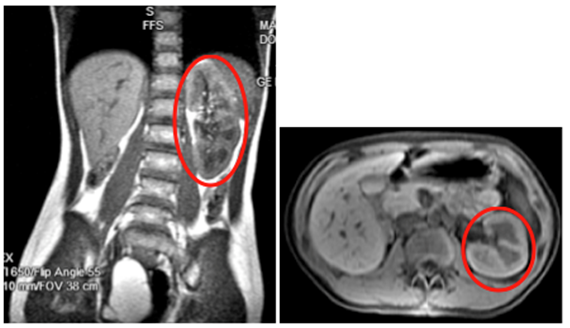

A 15-year-old Hispanic female, G0P0, initially presented with persistent sharp right lower quadrant pain. The patient was treated for pelvic inflammatory disease but, during further evaluation to rule out ovarian cyst and ovarian torsion, the patient was discovered to have severe primary dysmenorrhea, MDA and a solitary kidney. Ultrasound (Figure 1) and magnetic resonance imaging (MRI) (Figure 2) revealed a uterus didelphys with obstructed Hemivagina and Ipsilateral renal agenesis (OHVIRA syndrome) also known as Herlyn-Werner-Wunderlich Syndrome (Figure 3). Ultrasound indicated a 7.1 x 7.0 x 7.2 cm thick-walled right adnexal structure containing debris and fluids, which represented uterine didelphys with hematometra of the right-sided uterine horn (Figure 1 & 2). There was also a left uterine horn, which was oriented in the left pelvis and appeared unremarkable. Initial reproductive endocrinology and infertility recommendation was for 6 months of Leuprolide (Lupron) followed by continuous oral contraceptives (OCP) (with no placebo week), which the patient completed. However, the patient started getting her menstrual period every month (heavy and painful) while on OCP. The OCP was stopped and once the bleeding stopped the patient was re-started on 6 months of Lupron with norethindrone add back therapy, followed by continuous OCP (with no placebo week). The patient is currently scheduled to discuss the surgical option of hemi hysterectomy of the right rudimentary uterus versus resection of vaginal septum to open of obstructed Hemivagina.10

Figure 1 Patient 1: Pelvic Ultrasound, Transverse View 10/26/16: A 7.1 x 7.0 x 7.2 cm thick-walled right adnexal structure containing debris and fluid, this represent uterine didelphys with hematometra of the right-sided uterine horn. There is also uterine horn, which is oriented in the left pelvis and appears unremarkable.

Figure 2 Patient 1: Pelvic MRI: A normal-appearing uterine horn is seen in the left pelvis measuring 4.2 x 1.7 x 2.1 cm. A 9.7 x 4.9 x 4.7 cm lobular tubular thick wall cystic structure in the right pelvis is seen. Signal intensity suggests hemorrhagic contents. This lesion is contiguous with a similar but smaller dilated tubular structure extending to the right aspect of the posterior vagina. Findings are suspicious for uterine didelphys with hematometra of the right-sided uterine horn and cervix.

Figure 3 Patient 1: MRI of Abdomen with and without Contrast: Showing normal left kidney (Red Circle) with Right Renal Agenesis

In all three cases pelvic ultrasound was initial imaging tool. The ultrasound in case 1 (Figure 1) and subsequent MRI (Figure 2) shows a lobular tubular thick wall cystic structure in the right pelvis suggesting hemorrhagic contents extending into the right aspect of the posterior vagina and didelphys uterus. MRI of the abdomen depicts renal agenesis, demonstrating abnormal kidney development confirming HWW. As per the classification presented by Zhu and imaging, the patient has a class 1.2 OHVIRA.2 The ultrasounds in cases 2 and 3 (Figures 6 & 9 respectively) both demonstrate didelphys uterus with two cervices. The additional MRI in case 2, revealed two separate cervices and two uteri one with a retained IUD. MDA can be associated with a vaginal septum, more commonly vertical (Case 2 & Figure 5) but cases of a horizontal septum have also been reported (Case 1 & Figure 8).14